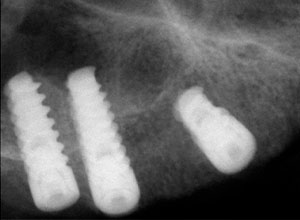

Radiografías periapicales donde se observa la posición de los implantes.